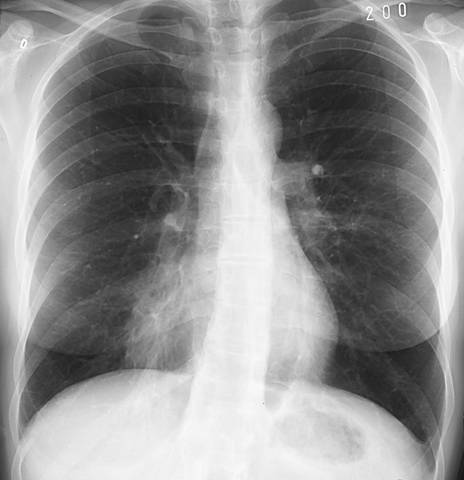

Lobar pneumonia (PA view). Lobar pneumonia. The postero-anterior radiograph shows an air bronchogram. The right margin of the heart is blurred. For lateral view, see Lobar Pneumonia (Lateral View).